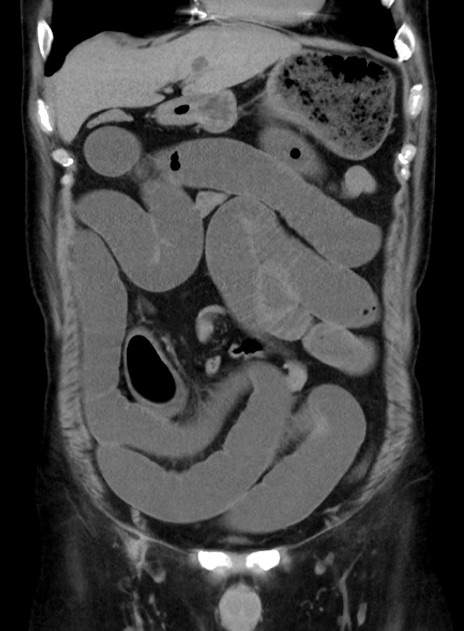

症例38(冠状断像)

【症例】70歳代 男性

【主訴】腹痛・嘔吐

【現病歴】昨晩より、嘔吐・腹痛あり。今朝になっても嘔吐あり。来院。

【既往歴】心臓バイパス手術、開腹胆摘、腸閉塞

【身体所見】BP 107/71mmHg、HR 116/min、腹部:平坦、軟、下腹部に軽度圧痛あり。反跳痛なし。

【データ】WBC 15100、CRP 0.32